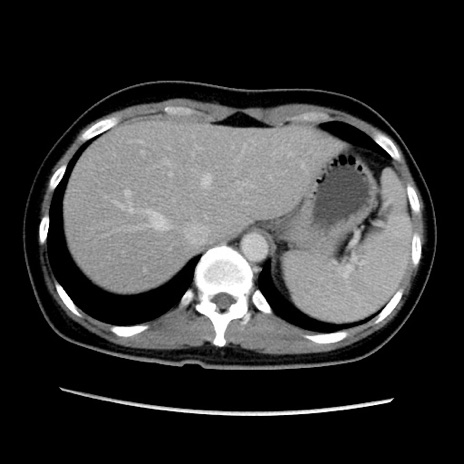

症例39(横断像)

【症例】40歳代女性

【主訴】上下腹部痛

【現病歴】2日目から下腹部痛あり。夜間は痛みで眠れなかった。昨日より上腹部痛と下痢が出現。臥位で痛みは軽快したため、休んでいた。本日になって臥位でも立位でも痛みが強くなってきたため救急要請。

【既往歴】子宮内膜症

【身体所見】部:平坦・軟、左上下腹部に圧痛あり、反跳痛あり。

【データ】WBC 21800、CRP 26.78